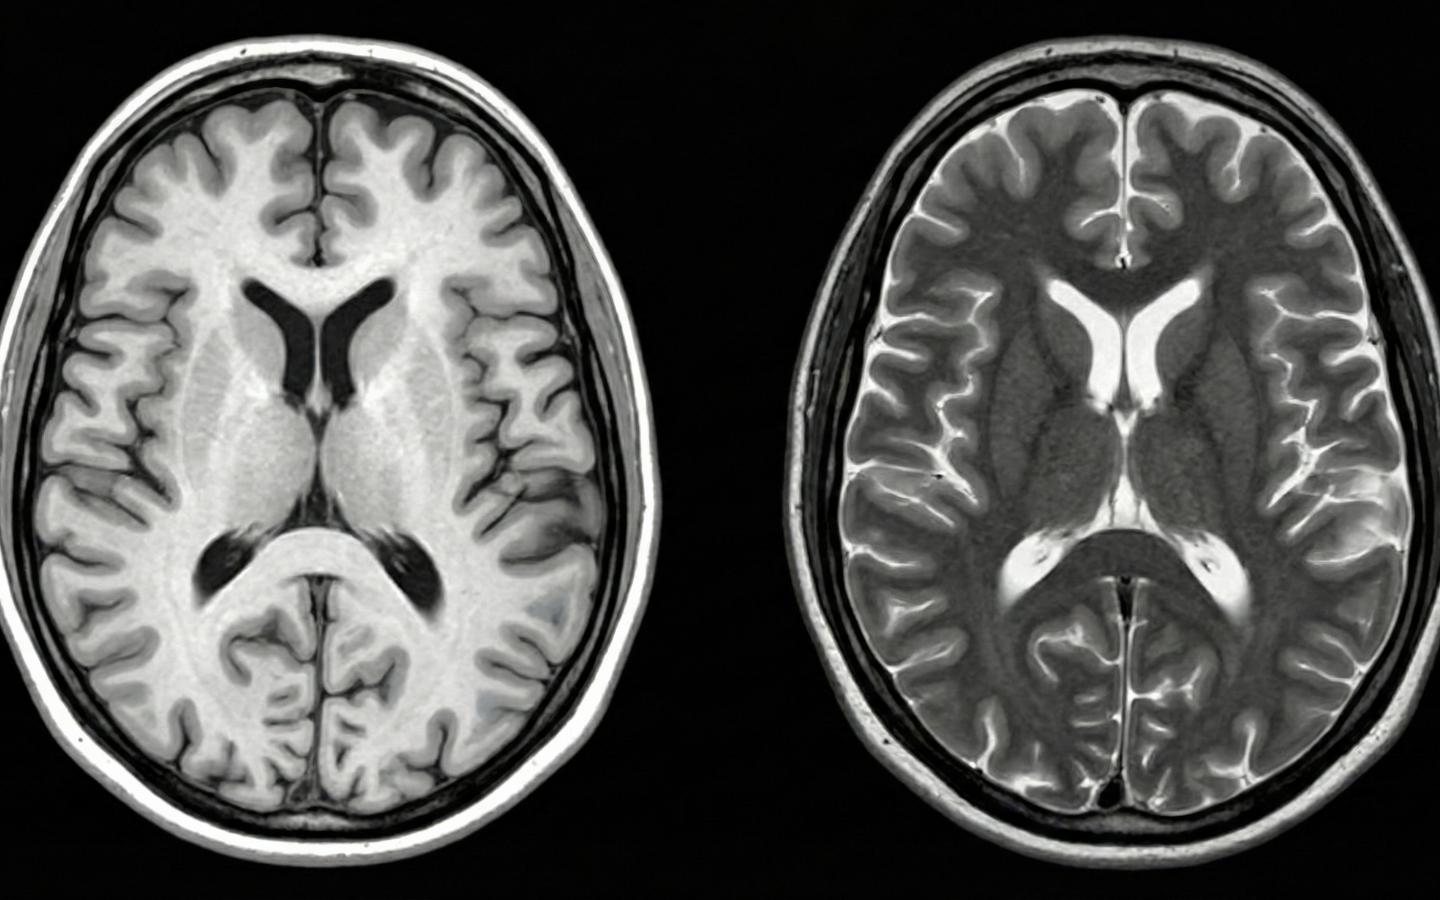

Neurological disorders are particularly devastating because the nervous system has traditionally been viewed as having limited capacity for repair. Once neurons die or myelin sheaths are damaged, conventional wisdom held that the damage was permanent. This is why most neurological disorders treatments focus on slowing progression rather than reversing damage.

But emerging research in regenerative medicine is challenging these assumptions. The nervous system does have regenerative capacity—it simply needs the right biological environment and signals to activate repair processes. This is where neurological disorders stem cells panama protocols at PCT Panama become transformative.

The fundamental approach of neurological disorders stem cells therapy is to shift the brain and spinal cord from a state of degeneration to one of repair. This isn’t about replacing every damaged neuron—it’s about creating biological conditions that support the survival of existing neurons, reduce harmful inflammation, and stimulate the formation of new neural connections.